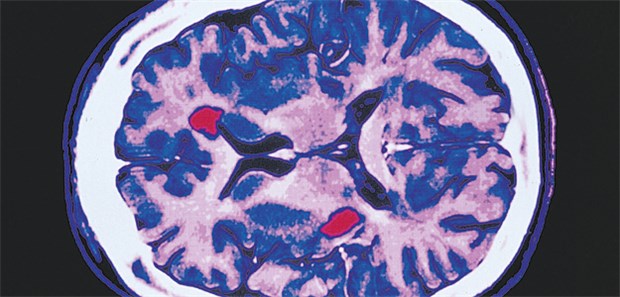

Gehirn mit MS-Läsionen: Medikamente senken die jährliche Schubrate.

© OKAPIA KG, Germany

Schubförmige MS

Vielfalt bei der Basistherapie